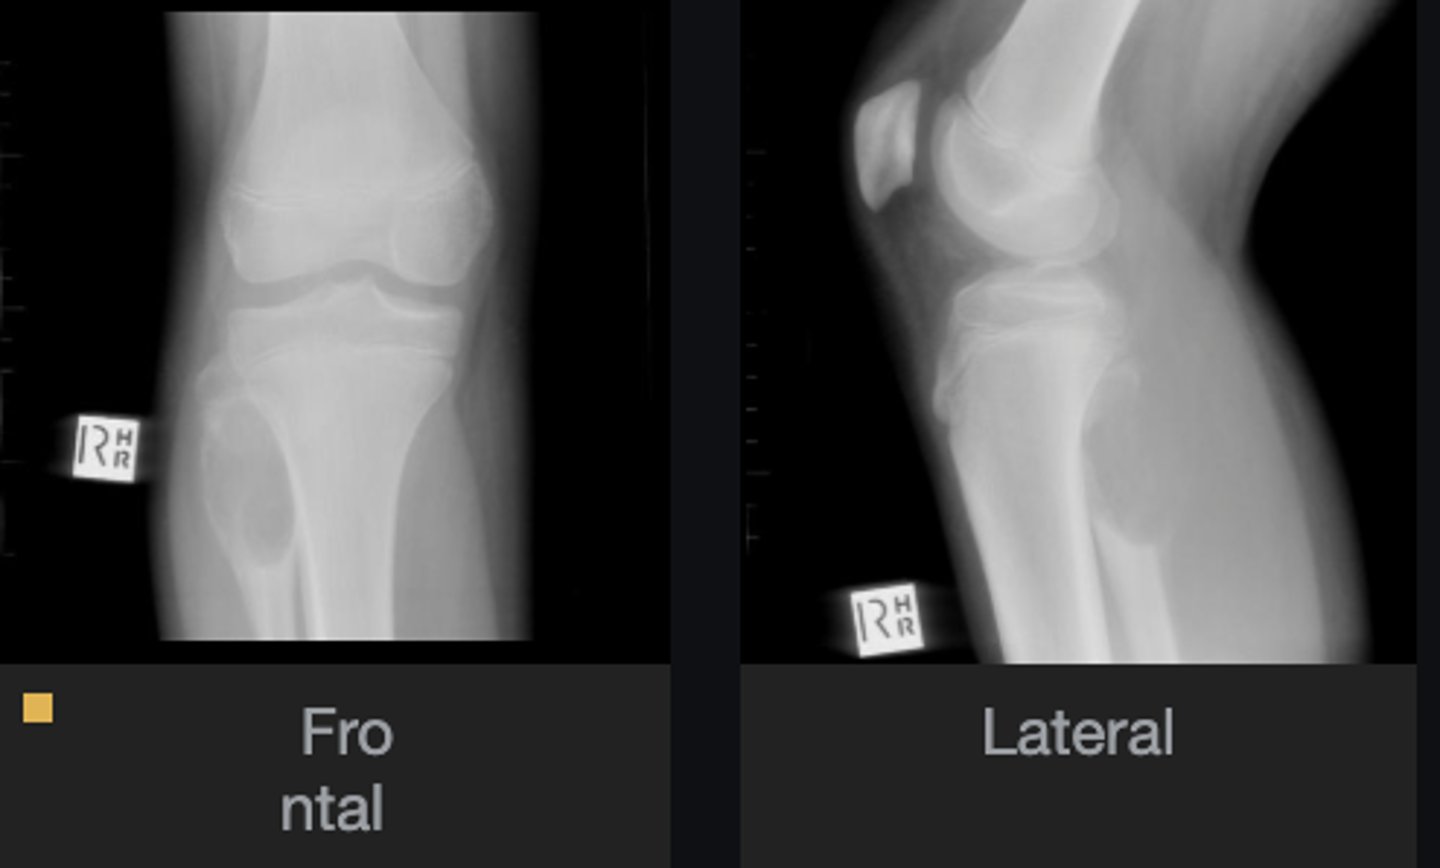

Lateral proximal tibia

Bone

<p>Bone</p>

- Longitudinal: epiphysis/metaphysis (up to joint surface)

- Eccentricity: eccentric

- Transverse: medullary

Location

<p>Location</p>

Monostotic

Mono/polyostotic

<p>Mono/polyostotic</p>

New cards

>1 cm

Size

<p>Size</p>

- Lytic

- Geographic

- Short zone of transition

Behavior

<p>Behavior</p>

- Cortical thinning

- Cortical expansion

Cortex

<p>Cortex</p>

Nothing visible

Matrix

<p>Matrix</p>

Giant cell tumor

Most likely diagnosis?

<p>Most likely diagnosis?</p>

Refer to orthopedist or oncologist

Next step?

<p>Next step?</p>

Could be aggressive (20%)

Concerns/complications?

<p>Concerns/complications?</p>